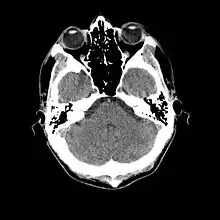

Normal human brain CT scan

More recently, computed tomography has played a large role in reconstructing endocasts. The procedure is non-invasive and has the advantage of being able to analyze a fossil in record time with little risk of damaging the fossil under review. CT imaging is achieved through the application of x-rays to produce tomographs, or sectional density images, which are similar to the images produced during MRI scans.[8] CT scans use slices approximately 1 mm thick to reconstruct a virtual model of the specimen.[9] This method is especially useful when a fossil cranium is occupied by a natural endocast that cannot be removed without destroying the skeletal portions of the fossil. Because the cranium and its contents are of different densities, the endocranial cavity and its unique traits can be reconstructed virtually.[8]